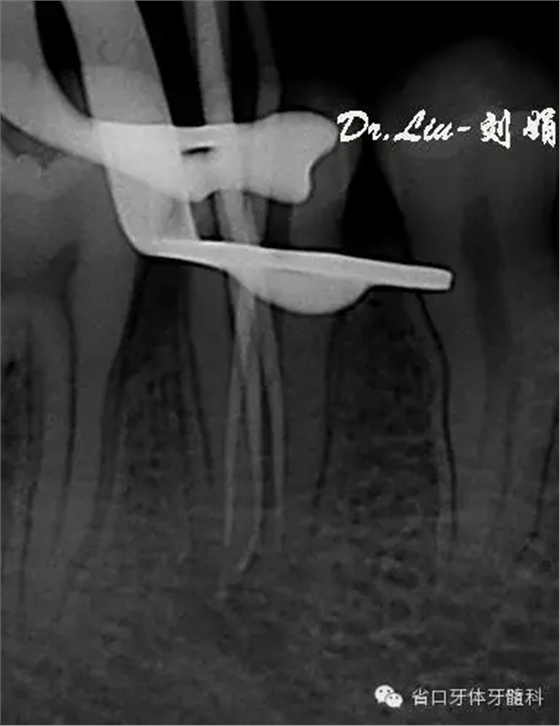

圖5:術(shù)中插尖片,見3根管

根管預(yù)備:顯微鏡下賽特力超聲ETB繼續(xù)去除根管上段及髓腔內(nèi)鈣化物,6#先鋒銼聯(lián)合pathfile銼和超聲逐步通根,測(cè)長:L=DB=MB=18mm,WAVE-ONE(Small)備根,紙尖干燥根管,氫氧化鈣糊劑暫封。